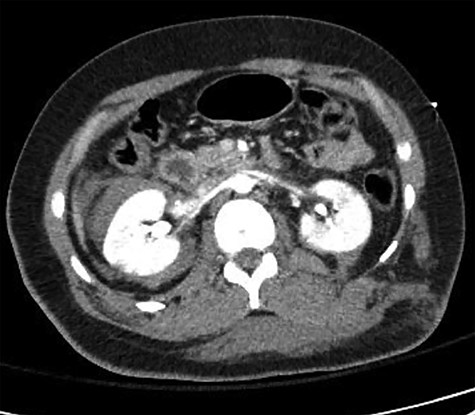

Fetal HR was measured at 135 bpm. Chest X-ray revealed a small apical pneumothorax and a fractured right clavicle. She was taken to the computed tomography (CT) scanner where CT-CAP with contrast revealed a Grade 2 liver laceration, Grade 3 splenic laceration and bilateral Grade 4 kidney injuries with extravasation of contrast on the renal delay, suggestive of urine extravasation. No pelvic fracture was found on imaging (Figs 1 and 2).